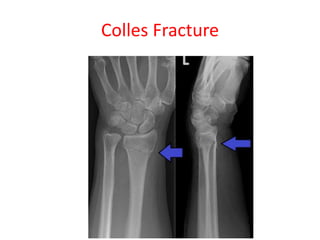

Colles Fracture

Colle’s fracture-

• Radius gets fractured about 2 cm above its lower end

due to fall on outstretched hand

Smith’s fracture- Reverse of Colle’s fracture

• If distal fragments gets displaced anteriorly

Colle’s fracture- • Radiusgets fractured about 2 cm above its lower end due to fall on outstretched hand Smith’s fracture- Reverse of Colle’s fracture • If distal fragments gets displaced anteriorly